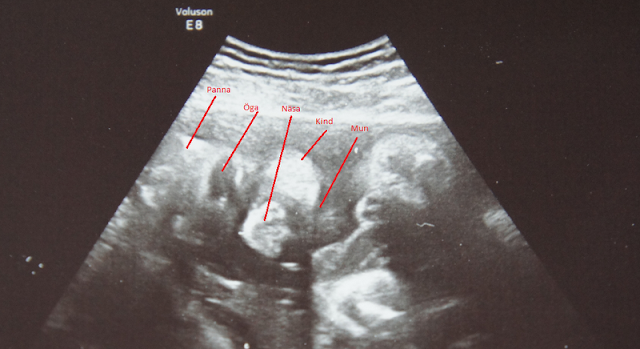

Idag så var det äntligen dags för besök på specialistmödravården igen. Visa sig när jag kom dit att jag skulle få träffa en annan läkare den här gången. Vet inte varför men skit samma tänkte jag vad gör det att blanda till en gubbe till i mixen.  Men Gud vilken trevlig läkare. Har nog aldrig träffat en så glad och trevlig läkare. Och jag har träffa många som mina år som sjuk. Han skämta och prata med en. Berätta hela tiden vad han gjorde och vad man vi såg på ultraljudet. Han fråga hur jag mådde. Han förklara även saker på ett enkelt och bra sätt. Man kände sig jätte bekväm med han. Fick veta att grabben är lagom stor han följer kurvan jätte bra på längd och så. Han väger bara lite för mycket typ 46g mot vad han borde. Men det är skit samma. Jag var mer rädd att han skulle vara för liten. Man får ju hela tiden höra hur liten jag är. Tyvärr så har väl inte det utvidgande njurbäckenet inte blivit bättre. Om jag förstod det rätt hade det väl blivit lite sämre.  Men fortfarande inom ramarna att man inte kommer göra något åt det. Men han skulle prata med en kollega som var mer insatt i det hela för säkerhetskull. Men det blir nog bra. Det rinner på bra på andra sidan så. Ska dit om två veckor igen nu. Vet att jag får komma till samma läkare då. Får hoppas att det blir han nu hela vägen.  Så sjukt jävla nöjd är jag efter idag. Frågade även om jag kunde få med mig en bild på lillen. Och självklart skulle vi fixa det tyckte han. Tyvärr var ju grabben lite blyg på den nya doktorn och skulle inte visa sig från sin bästa sida. Låg både med armar och navelsträng och flaxa i ansiktet. Men jag fick en bild med mig hem. (som han bjöd på =) ) Han gick även igenom bilden så jag skulle fatta vad man såg. Berätta för han att jag har väldigt svårt att se sånt där. Och han fick mig att fatta det. Jag ser grabben! Han la till och med sitt huvudet på bordet för att visa vilken vinkel han låg i. Det skulle aldrig den förra läkaren gjort.  Andreas har lite svårt att tyda bilden. Ser ni grabben?  Om ni lägger huvudet på sne åt vänster så ser ni han ligger lika dant med huvudet. Då har ni pannan på vänster sida sen ögat och sen ser ni hans äppelkind och munnen, näsan är den där vita saken som ser ut som ett tryne.  Inte den bästa bilden men man ser han.

Grabben i v.28 +1